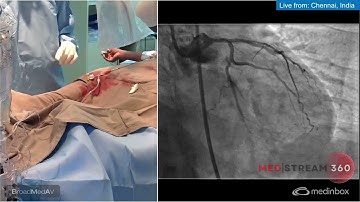

IVUS Guided PCI of LAD-D1 Bifurcation using Rotational Atherectomy and 2-Stent Mini-crush Technique